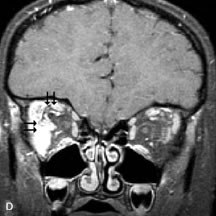

Intraorbital and intracranial optic nerve sheath meningiomas are usually isointense to cortical gray matter on Tl-weighted images and remain isointense on proton density studies (Fig. 15). Gd-DTPA is useful in delineating the intracranial extension of optic nerve meningiomas.7,47 The hyperostosis of bone and calcification associated with meningiomas are not demonstrated as well on MRI studies as on CT scans.20,37 Gd-DTPA–enhanced MRI also appears promising in the study of the permeability of the blood–brain barrier in selected optic neuropathies.22,48 MRI may reveal an enlarged optic nerve and some degree of contrast enhancement in cases of optic neuritis.49

Fig. 15. A. T1- and (B) T2-weighted MR scans demonstrate a mass causing fusiform enlargement of the optic nerve sheath complex. The peripheral portion of the mass, representing the meningioma, is isointense to brain on the T1-weighted scan and notably hypointense on the T2-weighted scan. The central portion of the mass, representing an edematous optic nerve, is very hyperintense on the T2-weighted scan (arrow), C and D. Postcontra fat-suppressed T1-weighted scans demonstrate intense peripheral enhancement of the meningioma surrounding the central nonenhancing optic nerve (arrow). Also note the enhancing Intracranial “dural tail” (double arrow).